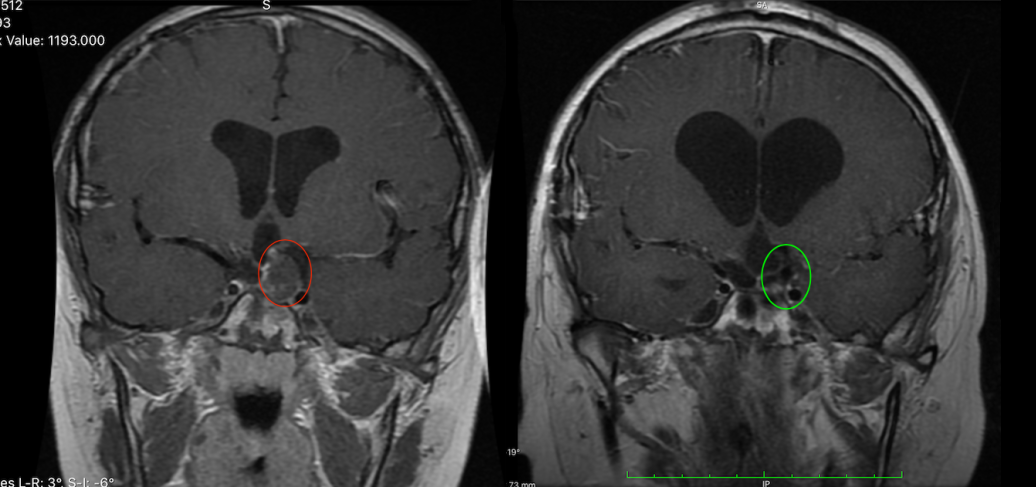

图为小俊手术前后对比,肿瘤顺利切除